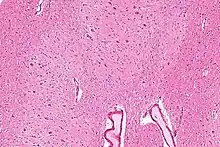

The dentate nucleus refer to a pair of deep cerebellar nuclei deep within the white matter of the cerebellum of the brain with a dentate – tooth-like or serrated – edge. The dentate forms the largest pathway between the cerebellum and the remainder of the brain.[1] It is the largest and most lateral of the four pairs of deep cerebellar nuclei, the others being the globose and emboliform nuclei, which together are referred to as the interposed nucleus, and the fastigial nucleus.

The architecture of cerebellum is a repeating fractal, so a slice anywhere in the cerebellum gives consistent neuronal branching patterns. The eight cerebellar nuclei, located within the deep white matter of each cerebellar hemisphere, are grouped into pairs, with one of each pair in each of the two hemispheres. As a chunk of tissue, the dentate nucleus with overlying cerebellar cortex makes up a functional unit called the cerebrocerebellum. Thus, there is a part of cerebellum that communicates exclusively with the dentate nucleus.[4]